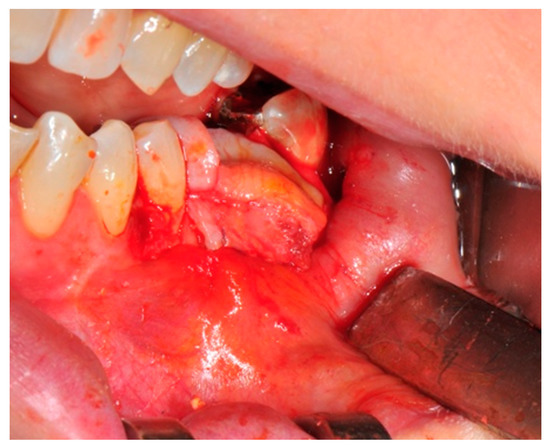

- Flap design: Soft tissue management should be as accurate as possible. The design of the flap should ensure a tension-free primary closure of the wound even after voluminous grafting of the defect. One option (preferred especially in wide vertical defects) is the execution of the so-called “poncho” flap. This technique includes a high vestibular incision of the mucosa, muscle and periosteum in order to undermine the preparation of the flap and to achieve its mobilization, followed by a deep incision in the buccal area with two additional vertical incisions that are performed at an appropriate distance from the occlusal area and the site of augmentation. After the incision, the preparation of a muco-periosteal flap and the remotion of scar tissue, a full thickness flap is raised until the bone defect is uncovered [17,18,19,20]. Finally, the positioning of the customized titanium mesh is passively tested to evaluate its fit intra-operatively (Figure 2, Figure 3, Figure 4 and Figure 5).